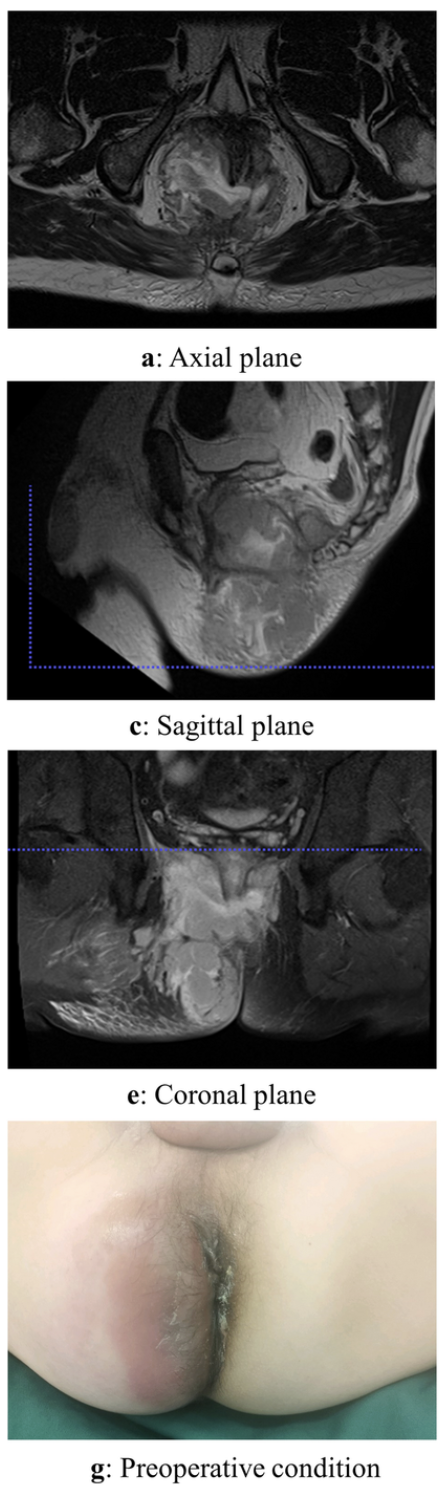

Most common anorectal abscess location is

A

Perianal

- located close to the anal verge, often posterior midline

- superficial tender mass that may or may not be fluctuant